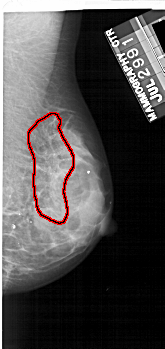

A_1734_1.LEFT_CC

LEFT_CC LINES 4936 PIXELS_PER_LINE 2296 BITS_PER_PIXEL 12 RESOLUTION 43.5 NON_OVERLAY

FILE: A_1734_1.RIGHT_CC.OVERLAY

TOTAL_ABNORMALITIES 1

ABNORMALITY 1

LESION_TYPE CALCIFICATION TYPE PLEOMORPHIC DISTRIBUTION SEGMENTAL

ASSESSMENT 4

SUBTLETY 3

PATHOLOGY BENIGN

TOTAL_OUTLINES 1

BOUNDARY